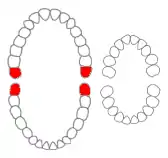

Wisdom teeth in the human mouth for permanent teeth. There are none in deciduous (children's) teeth. | |

Dental notation

There are several notation systems used in dentistry to identify teeth. Under the Palmer/Zsigmondy system, the right and left maxillary wisdom teeth are represented by 8┘ and └8, while 8┐and ┌8 represent the right and left mandibular wisdom teeth.[9] Under the FDI notational system, the right and left maxillary third molars are numbered 18 and 28, respectively, and the right and left mandibular third molars are numbered 48 and 38.[10] According to the Universal Numbering System the right and left upper wisdom teeth are numbered 1 and 16 and the right and left lower wisdom teeth are 17 and 32.[11]